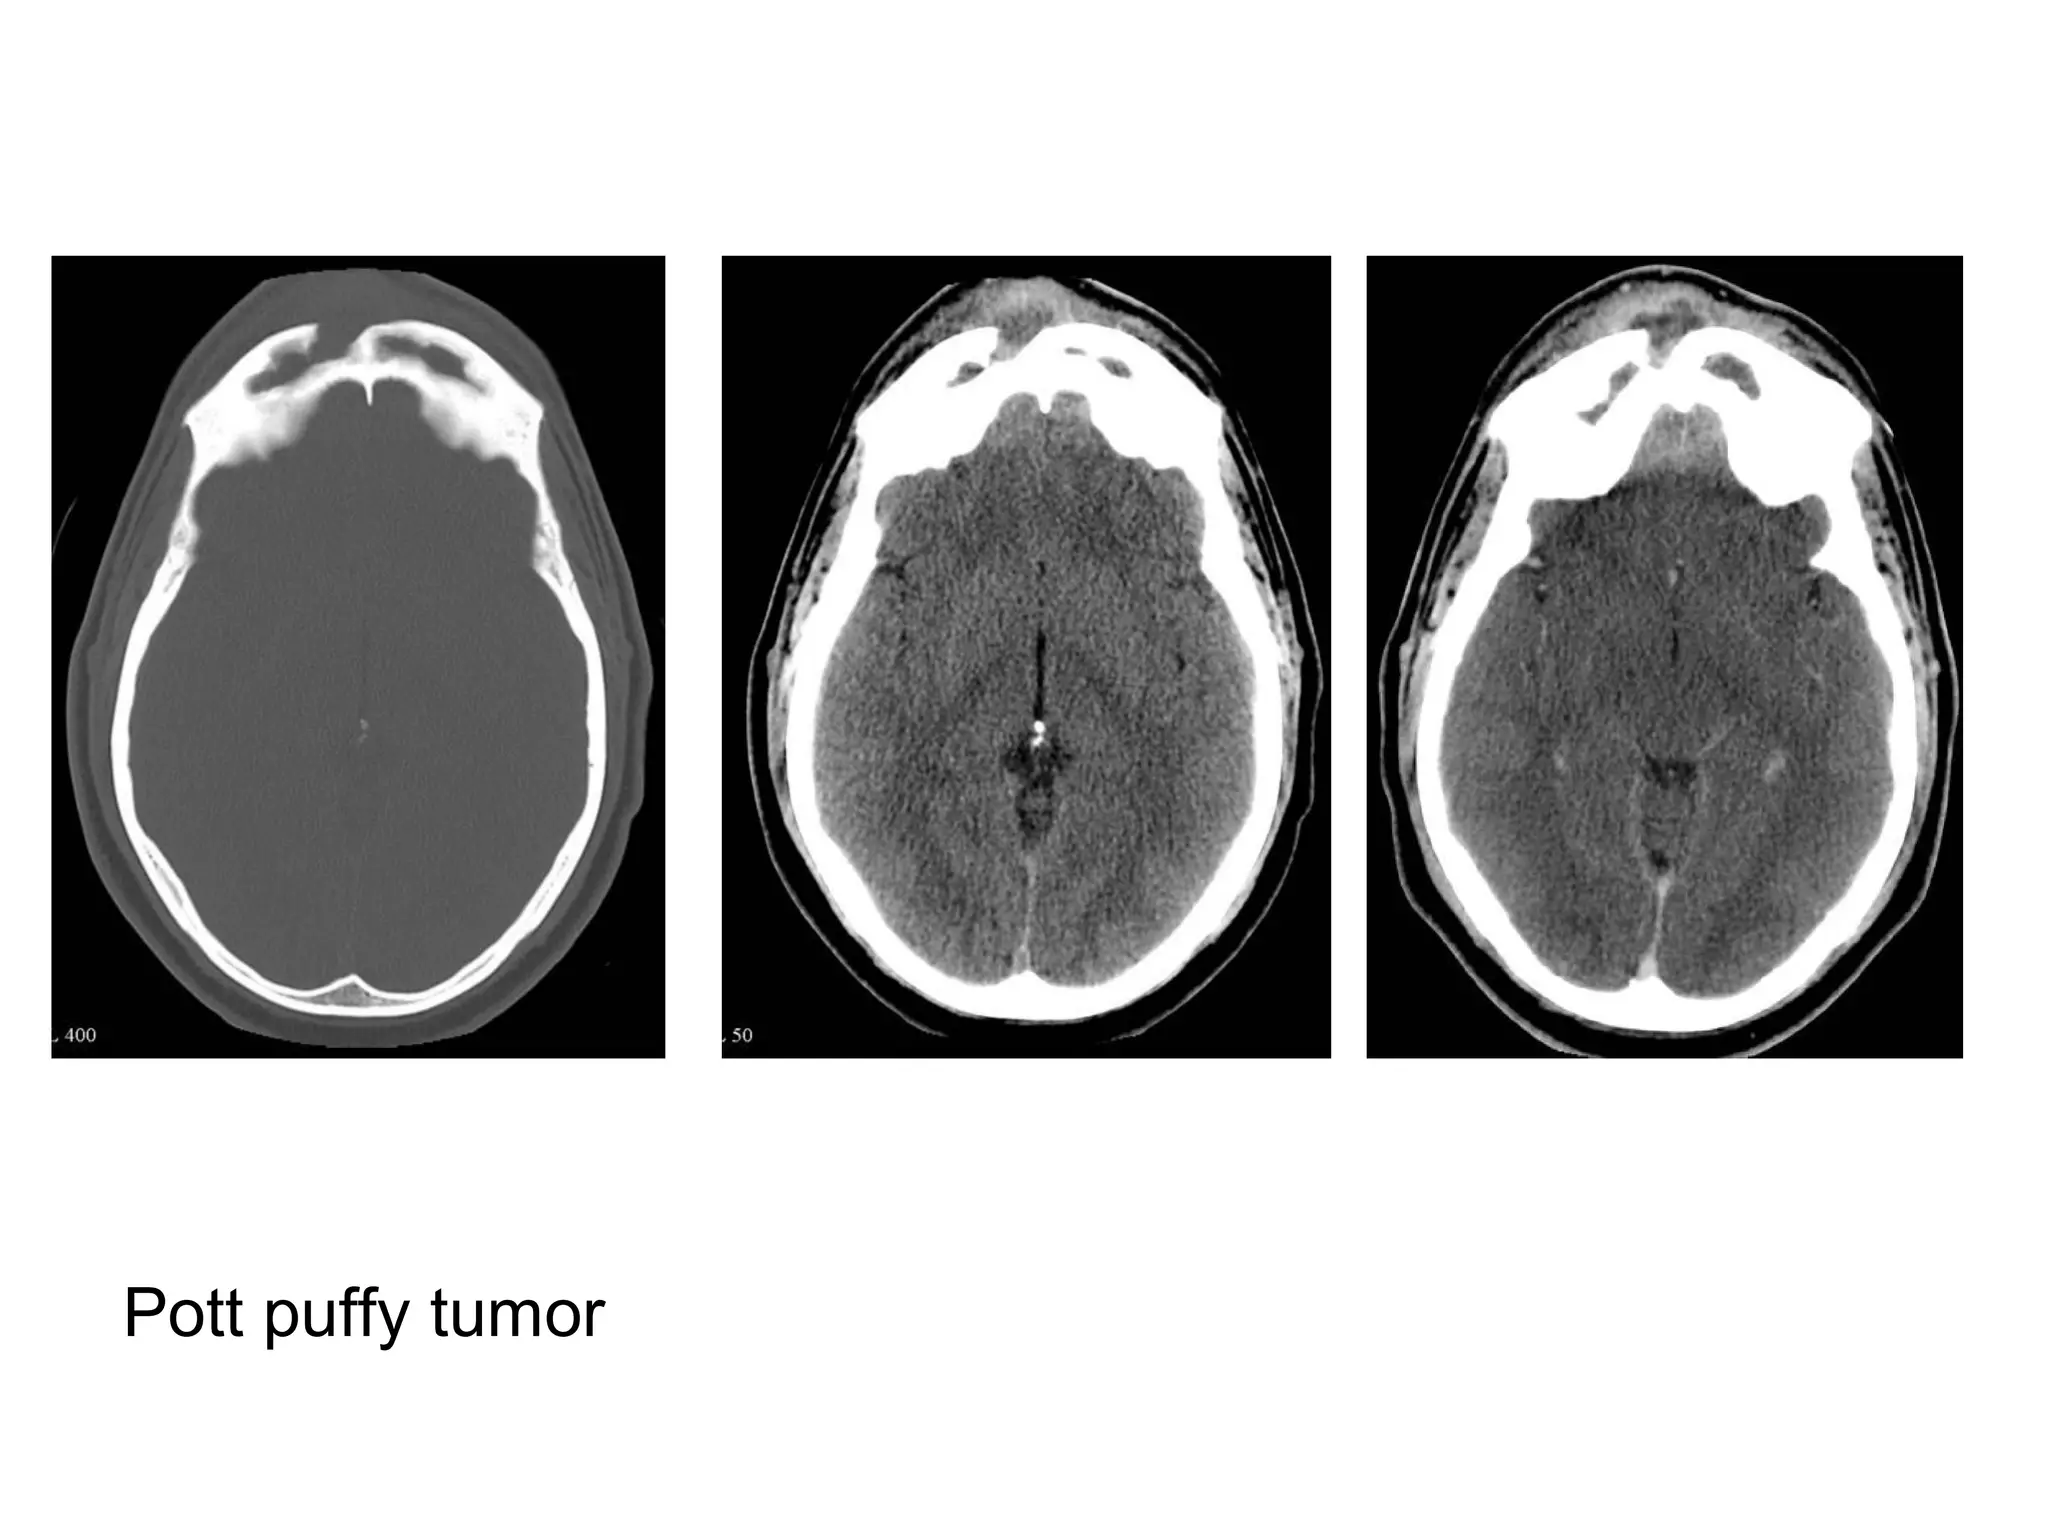

-Frontal sinus superficially (Pott puffy tumor), CT typically

demonstrates an opacified frontal sinus with stranding

and swelling of the overlying scalp, bone algorithm will

often demonstrate a defect in the anterior wall of the

sinus, contrast may demonstrate a focal abscess, and

may also allow intracranial complications to be

better delineated

Pott puffy tumor: a) Axial and b) sagittal CT+C in a soft tissue window showing

opacification of the frontal sinus with heterogeneous material (*) and a subperiosteal

abscess (white arrow) due to frontal sinusitis, note the small subdural fluid collection

(black arrow) indicating subdural empyema, c) Sagittal T1+C in another patient

showing a large subperiosteal abscess (long arrow), and a large extra-axial empyema

(short arrow), d) Axial CT image in a bone window in the same patient showing

erosion of the tabula externa (arrow) adjacent to the soft tissue mass, indicative of

osteomyelitis of the frontal bone

Pott puffy tumor

Pott puffy tumor, abnormal tissue in the frontal sinus (yellow arrow),

subperiosteal abscess (red arrow) and the fluid-fluid level (green arrow) in

the large intracranial lesion which has ring enhancement, all abnormalities

are continuous meaning there is frontal bony destruction, the restricted

diffusion also supports the diagnosis of brain abscess